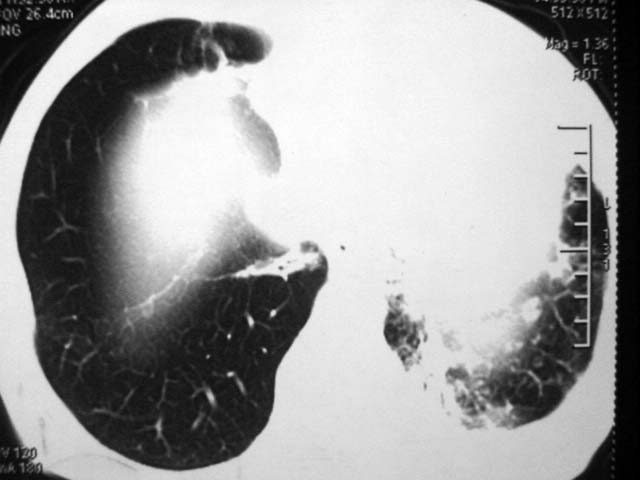

男,52岁,发热2月,糖尿病史。

抗结核治疗irpz方案,血糖未治疗,空腹15.9左右。症状无好转,左胸痛。

复查ct

2、双肺见多发片状及结节状高密度影,大多数病灶中心均见“空泡征”。

3、纵隔内淋巴结肿大。

结果:两肺继发性肺结核并曲霉菌感染。